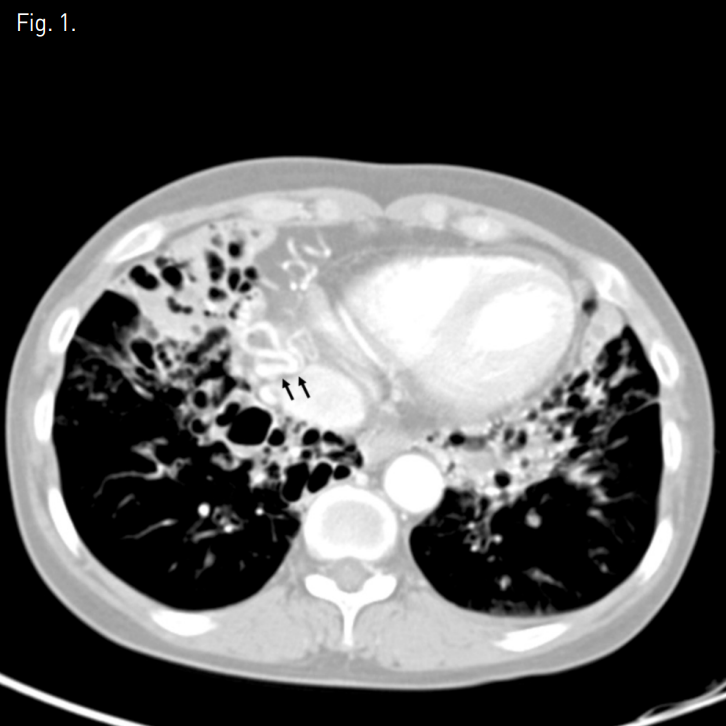

흉부 CT에서 양측 하엽과 우중엽에 기관지 확장증이 있으며 굵어져 있는 기관지동맥 및 우측 아래횡격막동맥이 관찰된다(Fig. 1). 대동맥조영술에서도 기관지동맥 및 우측 아래횡격막동맥이 굵어져있다(Fig. 2).

Fig. 2

Aortogram shows engorged right bronchial artery (arrowheads) and right inferior phrenic artery (arrows).